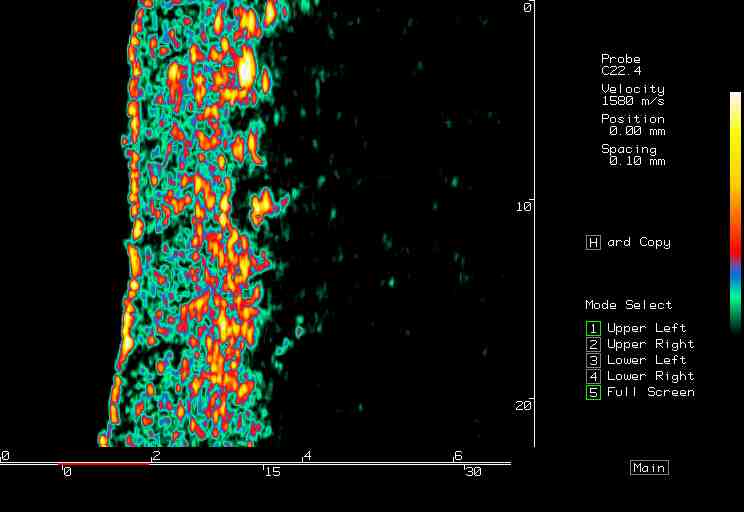

20 MHz 2D images

| Pressure wounds |  Pressure wound, edge |

Pressure wound, open |